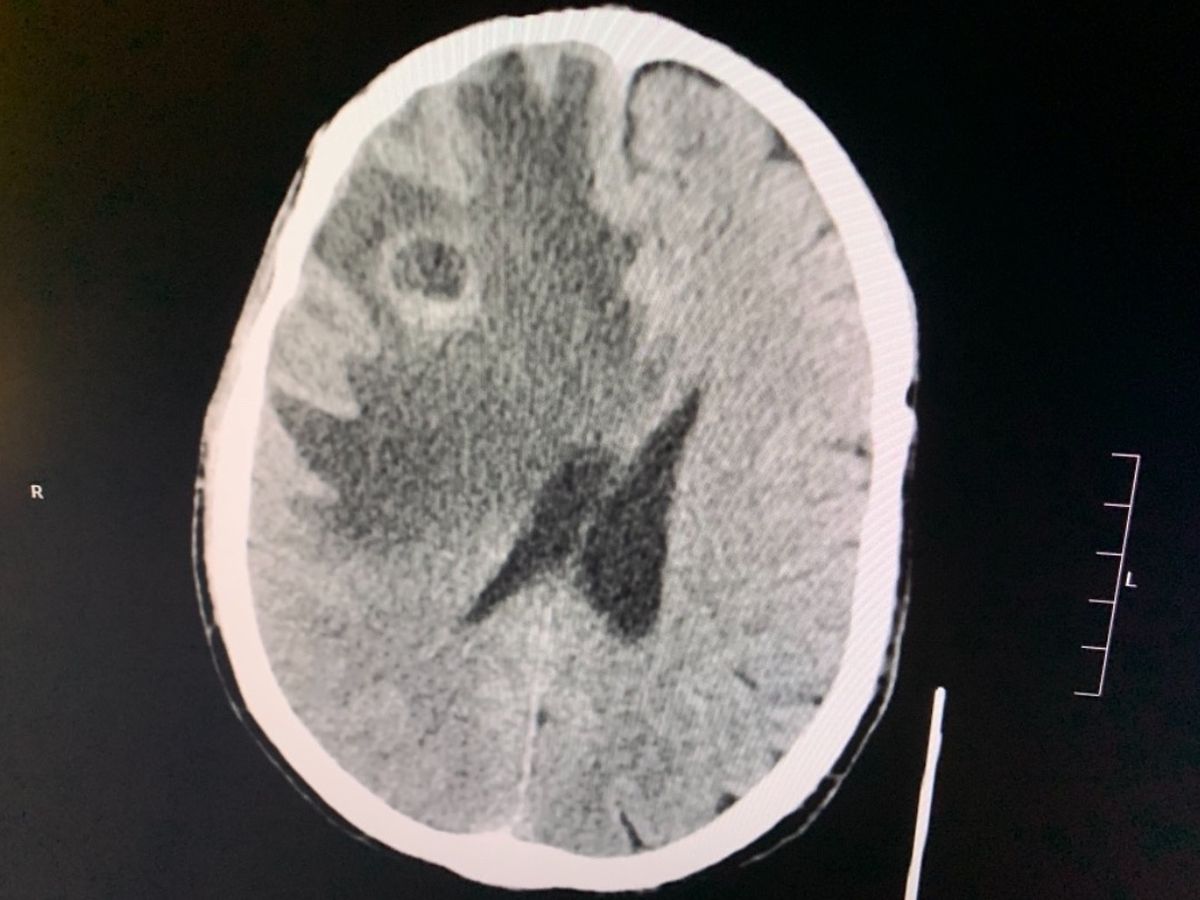

Her physical pain was mirrored by her depression and deep post-traumatic stress. Yet she continued the work she loves most until back problems recently forced her to resign also from 911 . Because of 911 she differs from PTS , fibromyalgia Disk generation degeneration disease and now can and and numerous tumors in the brain cancer and throughout her body .

Beginning this past July 4 weekend, while considering her next steps, Mo began suffering severe headaches and had multiple bad falls over the next several weeks, finally sending her to the ER. A brain tumor was found, and Mo was rushed to Maryland University Hospital for emergency surgery.

A lung tumor was also found. Like far too many other 9/11 heroes who worked on the front-lines, Mo has been thrown into a fight for which she never asked for , and which no one deserves.

Doctors are evaluating various protocols that will best battle these multiple tumors, and lesions . She will begin immuno-suppressive and or Chemo treatment once all biopsies are compleat - Mo is due to start the second such treatment shortly.

Her physical pain was mirrored by her depression and deep post-traumatic stress. Yet she continued the work she loves most until back problems recently forced her to resign also from 911 . Because of 911 she differs from PTS , fibromyalgia Disk generation degeneration disease and now can and and numerous tumors in the brain cancer and throughout her body .

Beginning this past July 4 weekend, while considering her next steps, Mo began suffering severe headaches and had multiple bad falls over the next several weeks, finally sending her to the ER. A brain tumor was found, and Mo was rushed to Maryland University Hospital for emergency surgery.

A lung tumor was also found. Like far too many other 9/11 heroes who worked on the front-lines, Mo has been thrown into a fight for which she never asked for , and which no one deserves.

Doctors are evaluating various protocols that will best battle these multiple tumors, and lesions . She will begin immuno-suppressive and or Chemo treatment once all biopsies are compleat - Mo is due to start the second such treatment shortly.